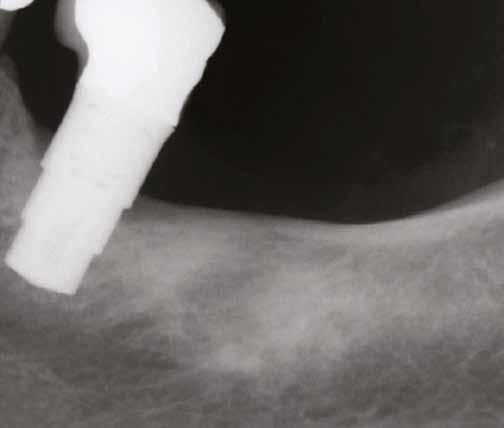

7. ábra: Röntgenfelvétel a behelyezett pótlással.